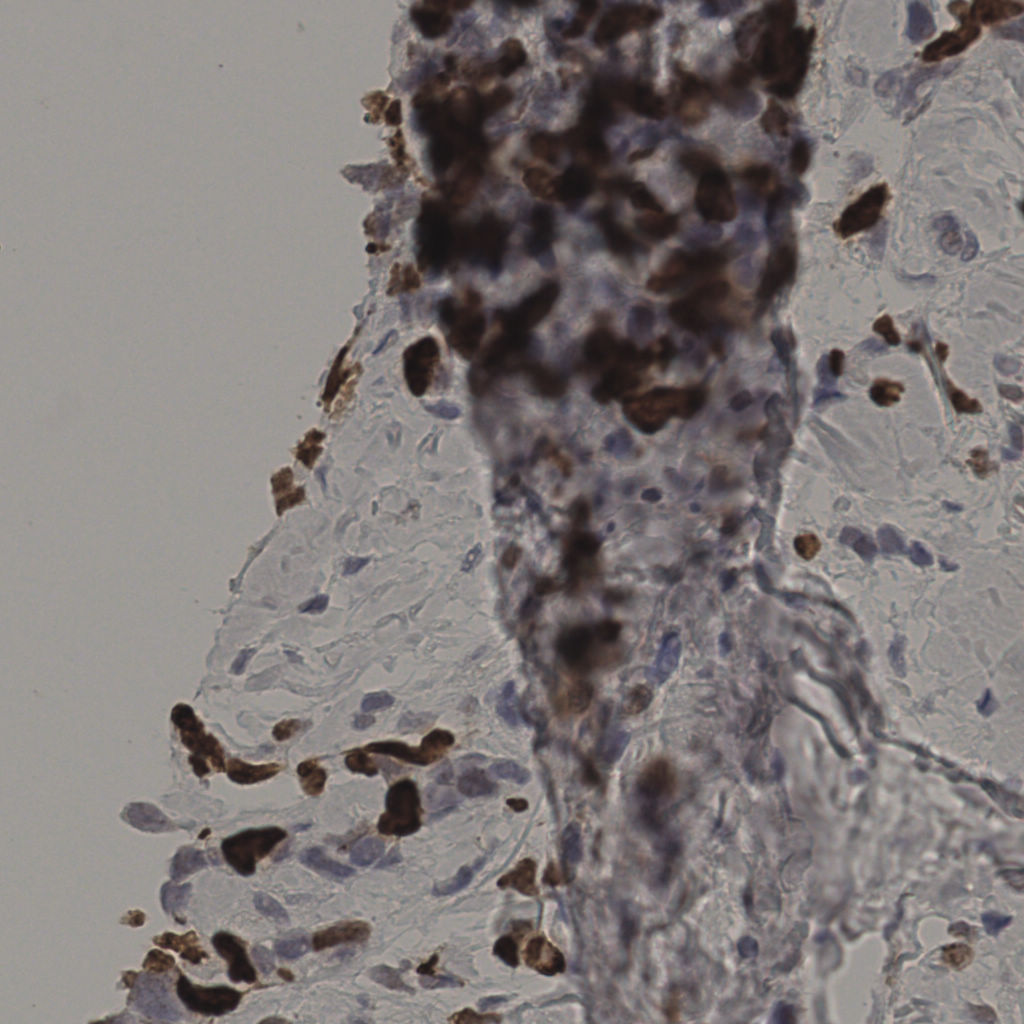

17.75%

Ki67 指数

阴 7986 阳 1723

切片统计

总切片 2640

有效 412

已标记 412

有效率 16%